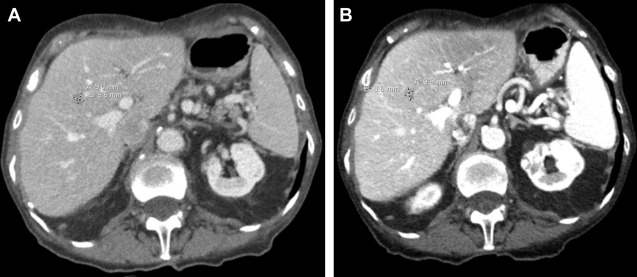

Surveillance CT scans for a patient with small bowel neuroendocrine tumor metastatic to the liver demonstrating stable/nonresponsive disease to peptide receptor radionuclide therapy (PRRT) during the interval following (A) PRRT cycle #2 to (B) completion of PRRT cycle #4.